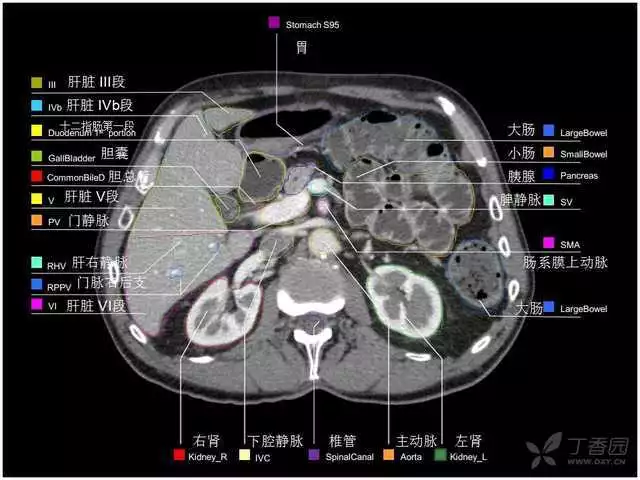

其实你离掌握上腹部 CT 影像只有一套高清实用图谱的距离,下面把我最喜欢的这本图谱分享给大家,为了方便阅读,我加了中文标识。后面附赠几张血管相对位置解剖关系图片,帮助大家理解(文中多图,建议在 wifi 环境下查看)。